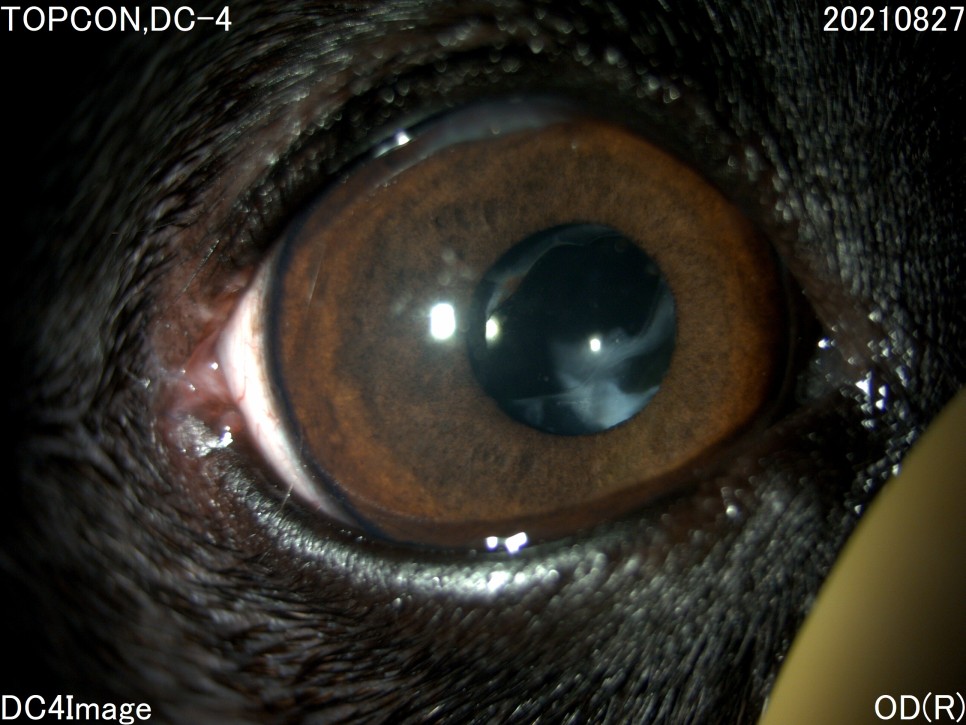

- 세극등 현미경 검사

양안의 백내장이 심하게 진행되고 있었지만 다행히도 당뇨병 관리를 하고 있는 전주 24시 동물병원은 당뇨병 관리 뿐만 아니라 눈 관리도 계속해 주셨기 때문에 내원 당시에는 양안 모두 심한 포도막염은 없었습니다.

그러나 왼쪽 눈은 백내장 단계 중 4기인 과성숙 단계로 진행되었으며, 이전에 앓고 있던 심한 포도막염에 의해 홍채의 일부가 수정체에 유착되어 있는 것이 보였습니다.

백내장이 오래 되거나 염증 반응이 심한 경우는 수정체를 감싸는 낭포 섬유화가 일어나 낭 자체에 백내장 파편이 붙어 있을 수 있는데, 자녀분이 바로 그런 상태였습니다.이런 경우 수술이 어려울 뿐만 아니라 수술 후 합병증의 발생률도 더욱 높아질 수 있습니다.